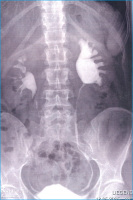

Die roboterassistierte laparoskopische Pyeloplastik analog Anderson-Hynes

Journal für Urologie und Urogynäkologie 2006; 13 (4) (Ausgabe für Österreich): 14-16 Journal für Urologie und Urogynäkologie 2006; 13 (4) (Ausgabe für Schweiz): 14-16 Volltext (PDF) Summary Abbildungen